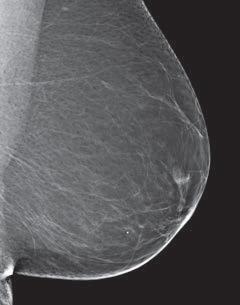

Dense breast tissue, as seen on a mammogram, has more fibrous connective tissue and glandular tissue, and less fatty tissue. It is often inherited, but menopausal hormone therapy, and low body mass index are factors associated with breast density. Dense breast tissue is a risk factor for breast cancer, and a radiologist can tell if a woman has dense breasts.

A mammogram uses X-rays (ionizing radiation) to create images of the inside of the breast to check for cancer and other conditions. It can be used for screening to detect cancer, for instance, before there’s a lump in the breast, or to assist in the diagnosis of cancer. Radiologists use mammograms to interpret, and classify breast density into four categories.